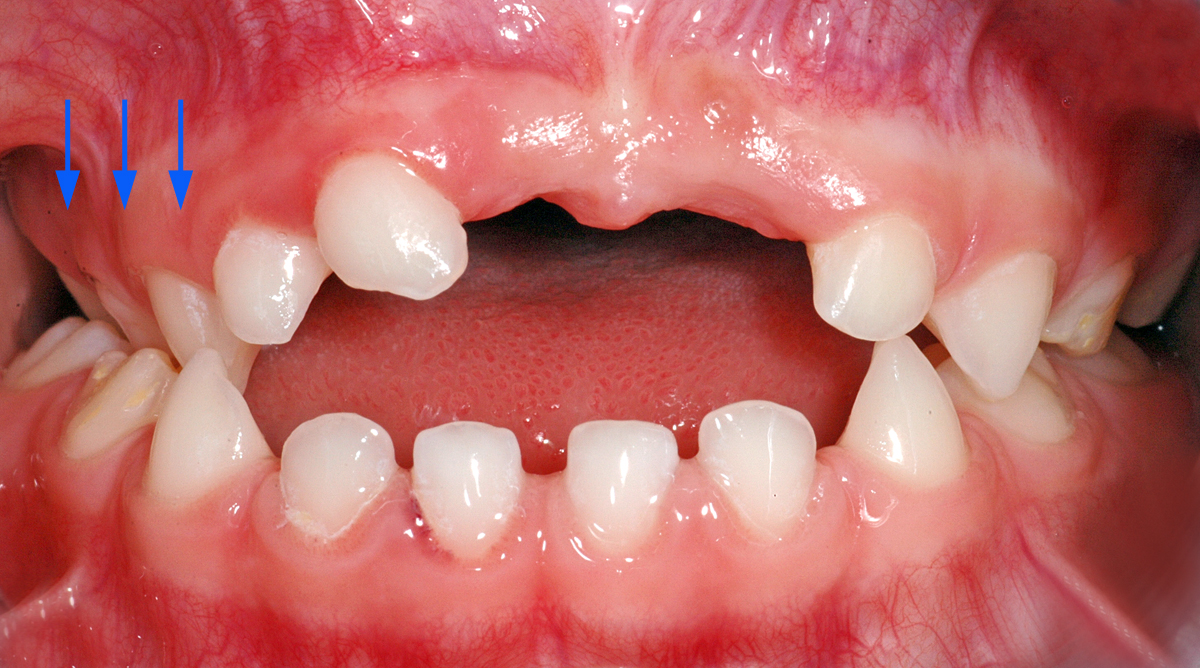

Anbei ein Fall einer 4½ Jahre alten Patientin, die Befunde in folgenden Bereichen aufzeigt: Unfallfolge mit Zahnverlust ( Punkt 1), überzählige Zähne (Punkte 2 und 3), Zahnstellungsabweichungen (Punkte 4 und 5).

4. Kreuzbiss im Seitenzahnbereich auf der rechten Seite (blaue Pfeile im Bild).

5. Offener Biss in der Front (das heisst, dass die Schneidezähne beim Zusammenbeissen nicht «übereinander» oder aneinander kommen; ist im Bild blau markiert).

Klinisches Bild

Ansicht von vorne. Darauf sind die Zahnstellungsabweichungen und der überzählige Zahn zu sehen. In den weiteren Bildern sind die Befunde markiert.

Kreuzbiss rechts (blaue Pfeile)

Offener Biss in der Front (blau markierte Zone)